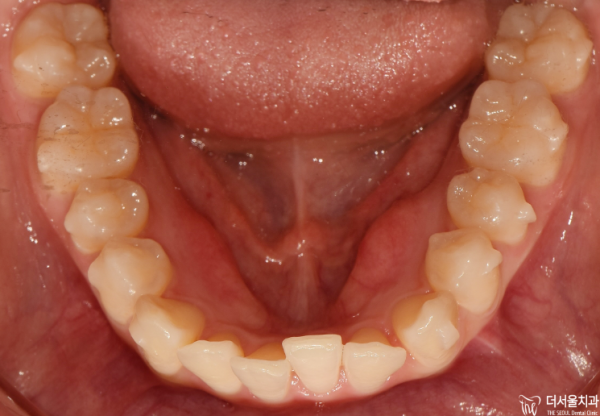

이렇게 교합면을 보면 앞니들이 위 아래 모두 삐뚤빼뚤한

총생을 보이고 있습니다.

If you look at the occlusal side, the front teeth are all crooked.

He's living his whole life.